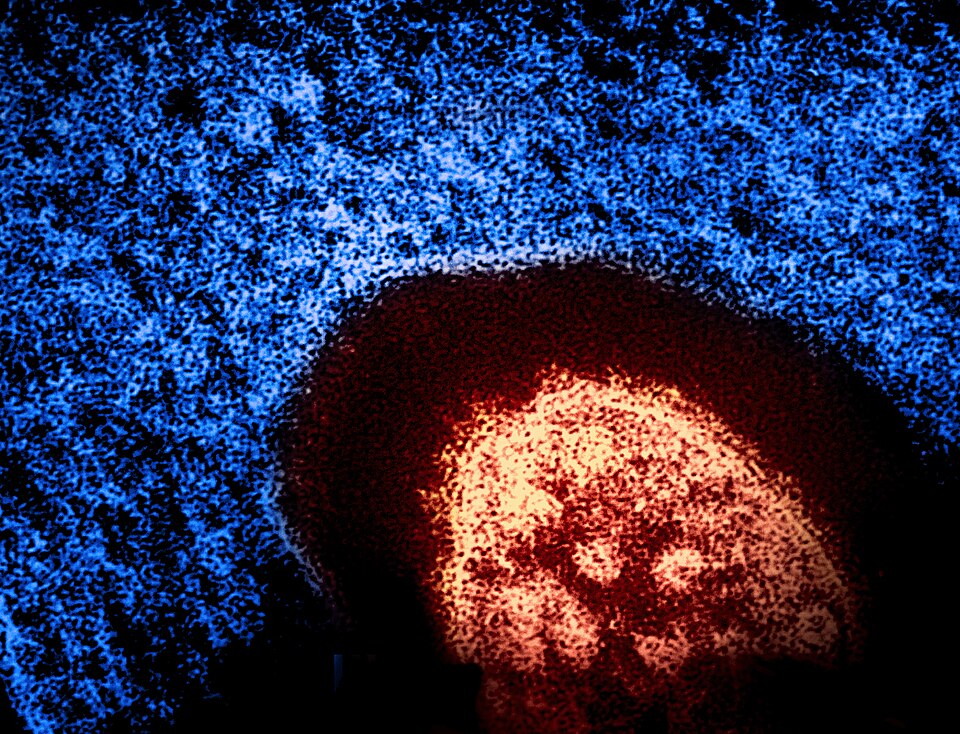

The measles resurgence in the United States has highlighted weaknesses in vaccination rates and has raised renewed questions among public health experts about public confidence in vaccination and disease prevention. It has been more than two decades since measles was declared eliminated in the United States, but its reemergence has threatened the concept of herd […]